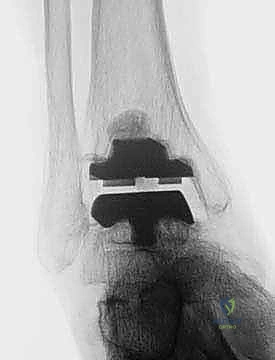

FIG 6 • The TNK ankle replacement for rheumatoid arthritis of the ankle (cemented replacement). A. Preoperative AP view. B. Preoperative lateral view. C. Postoperative AP view 2 years 6 months after the surgery. D. Postoperative lateral view.